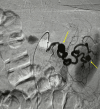

Figure 2

Figure 2. Angiogram showing two splenic artery aneurysms. The right arrow is the ruptured splenic artery aneurysm

Figure 3

Figure 3. Statue-post coiling of the splenic artery aneurysm